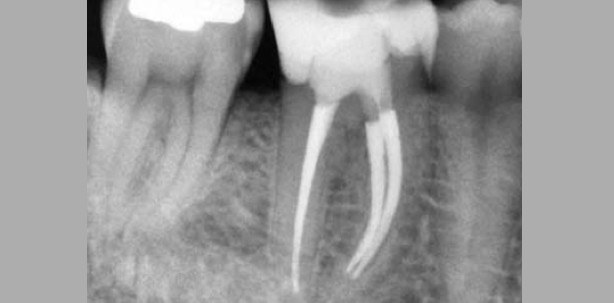

In folgendem Fall kam der Patient mit Schmerzen in unsere Praxis. Das angefertigte Röntgenbild zeigte eine ausgedehnte Approximalkaries, welche auf eine Beteiligung der Pulpa schließen ließ. Nach Kariesexkavation wurde das eröffnete Pulpenkavum zunächst abgedeckt und der Zahn mit einer adhäsiven Kompositfüllung aufgebaut. Danach erfolgte unter Kofferdam und optischer Vergrößerung (Zeiss OPMI PROergo) die Trepanation des Zahnes. Nach Darstellung der Kanaleingänge und Bestimmung der Arbeitslänge wurden die Kanäle mit dem TF Adaptive-System aufbereitet. Nach Durchführung des Spülprotokolls mit Anwendung des Unterdruckspülsystems EndoVac (SybronEndo) erfolgte die Obturation als thermisch vertikale Kompaktion mit Resilon (Real Seal SE). Zum Abschluss wurde der Zahn noch adhäsiv mit Komposit verschlossen.